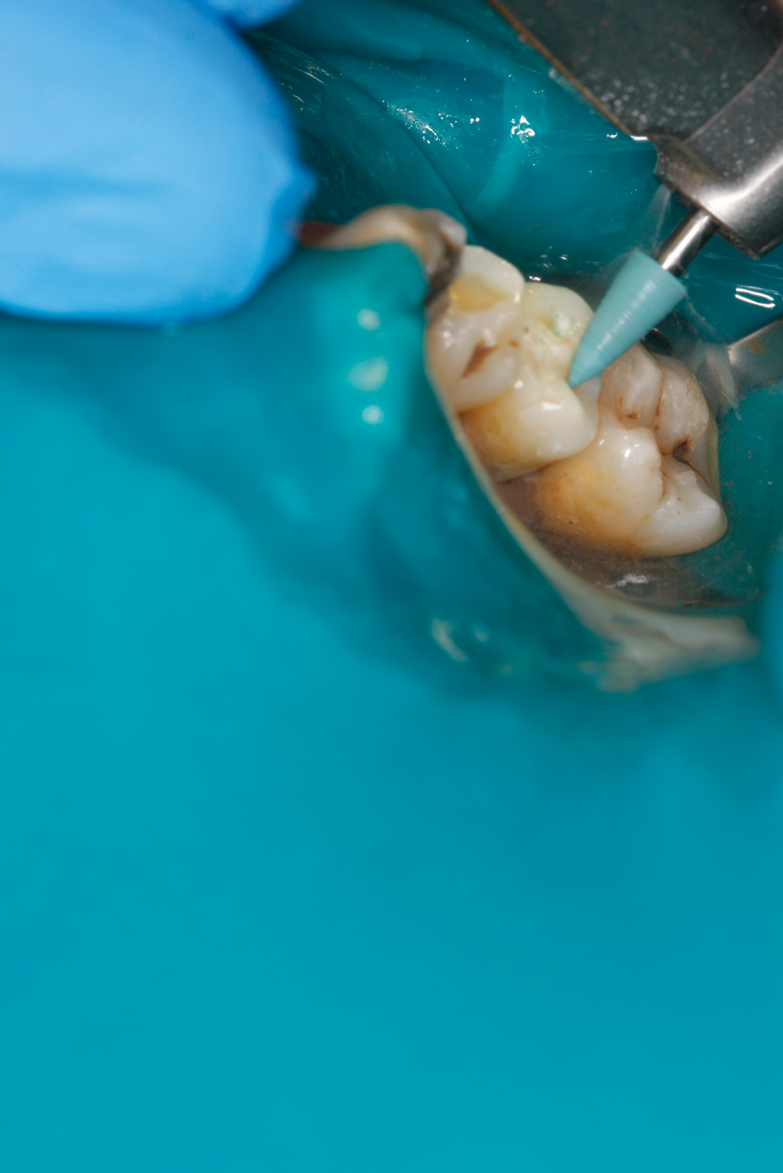

Fig 35. Injection filling of cavity preparation with dual-cure bulk-fill flowable composite to a slight overfill.

Figure 35

A deep distal occlusal preparation was performed and a matrix band (Paraband, Practicon) was placed again, such that no wedge needed to be placed (Figure 32). The Groman Etchmaster was utilized to remove biofilm as previously shown in Figure 12. A total etch technique with 37% phosphoric acid was employed (Figure 33), and after thorough rinse and damp dry, a universal adhesive (Scotchbond Universal, 3M) with MDP was applied and light-cured 40 seconds at 1,200 mw/cm2 due to the depth of the box form (Fig- ure 34). Figure 35 shows the dual-cure bulk-fill flowable composite (Bulk EZ Plus, Zest Dental Solutions) being injected into the deep box with a 20-gauge bendable needle. It is important to keep extrusion pressure on the plunger while withdrawing the needle to prevent bubbles or voids in the composite interface with the tooth structure. Overfilling by approximately 10% and smoothing the surface only with brushes promotes good marginal seal (Fig- ure 36). It is critical to not disturb the occlusal surface of any dual-cure bulk-fill flowable with an attempt to "soft sculpt," as that may create marginal voids.